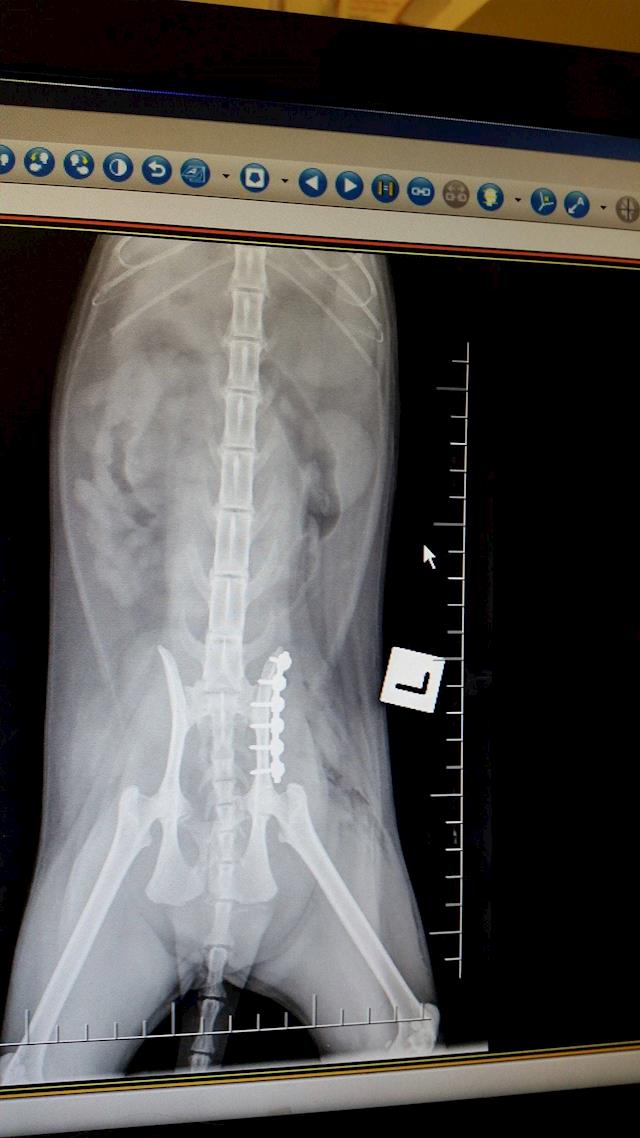

They set her fracture, and it seems it was her left pelvis, I had thought it was the right. So she wasn't lying on the broken side at the vet's the other day; she was lying on the not-broken side.

This evening, first working day of the week (Monday was Queen's Birthday weekend) I saw the surgeon. His name is David, and he put the x-rays up on screen again, and took me through the process of what would be done. She will have something called a 'string of pearls' which I visualise as a meccano piece with lots and lots of bolts. The bolts go into the bone, I guess they must be self-tapping. They hold the two slivers together.

He explained that so many days after the event (it will be nearly a week on Wednesday) all her muscles will have tightened and it will be very difficult to get the pelvis back to where it belongs; but he should at least be able to make a good job of widening the pelvis enough for faeces to go through it. See the x-ray attached, for what has happened. The pelvis has snapped off and shunted up forwards into the actual pelvis area.